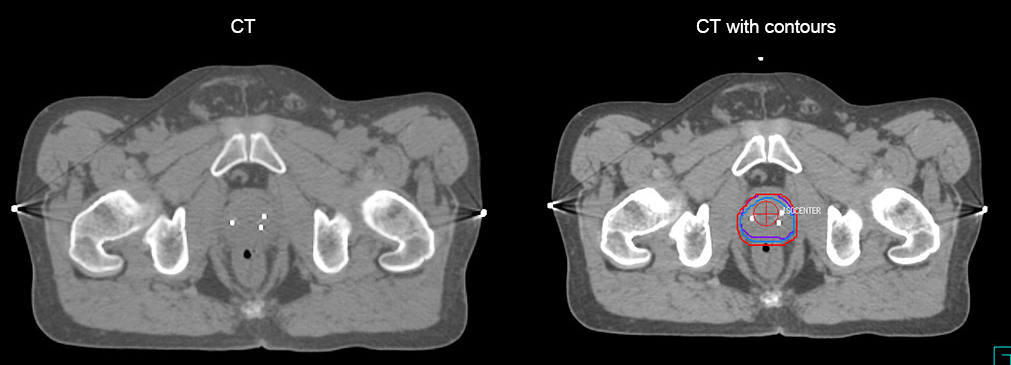

“The biggest problem for CT-based planning, especially in prostate, is you can’t see the cancer very well,” says Dr. Stevens. “On CT it can be quite challenging to see the edge of the prostate especially at the apex. When the edge of the prostate can’t be delineated well on CT, radiation oncologists will increase their margins a little bit so they don’t miss it, but that can also increase toxicity.”

“Using MR, the prostate is well delineated. We quickly see the edges of cancerous tumors like in prostate cancer, and as normal structures can be defined, we can optimize the treatment plan to protect these organs and their normal function. This can potentially improve the outcome. And it improves workflow as well. We can contour more quickly, confident that the tumor is going to be in the field.”

“There are some general challenges in RT imaging – even with CT – such as imaging geometry and positioning accuracy. Positioning is extremely important in RT, because we need reproducibility between imaging and treatment position. We also need accurate geometry so we can be sure our treatment plan is properly delivered during the treatment,” says Dr Yan.

“The Ingenia MR-RT configuration includes an external laser positioning system for patient alignment and a flat tabletop for imaging the patient in treatment position. Ingenia MR-RT also came with a special QA package for regular monitoring of precision. Our Ingenia 3.0T scanner achieves good geometric accuracy – within a millimeter for most patients – and the phantom measurement is even better,” he adds.

“When a patient registers, first CT simulation and MR simulation are done, followed by CT-MR registration on Pinnacle3. Then the target and normal organ delineation is performed on MR images. Meanwhile we create a reference CT image for online treatment and localization correction. During the treatment phase we can perform additional MRI scans to visualize the anatomy changes and create an adaptive plan. This plan basically adapts the treatment plan to the changes.”